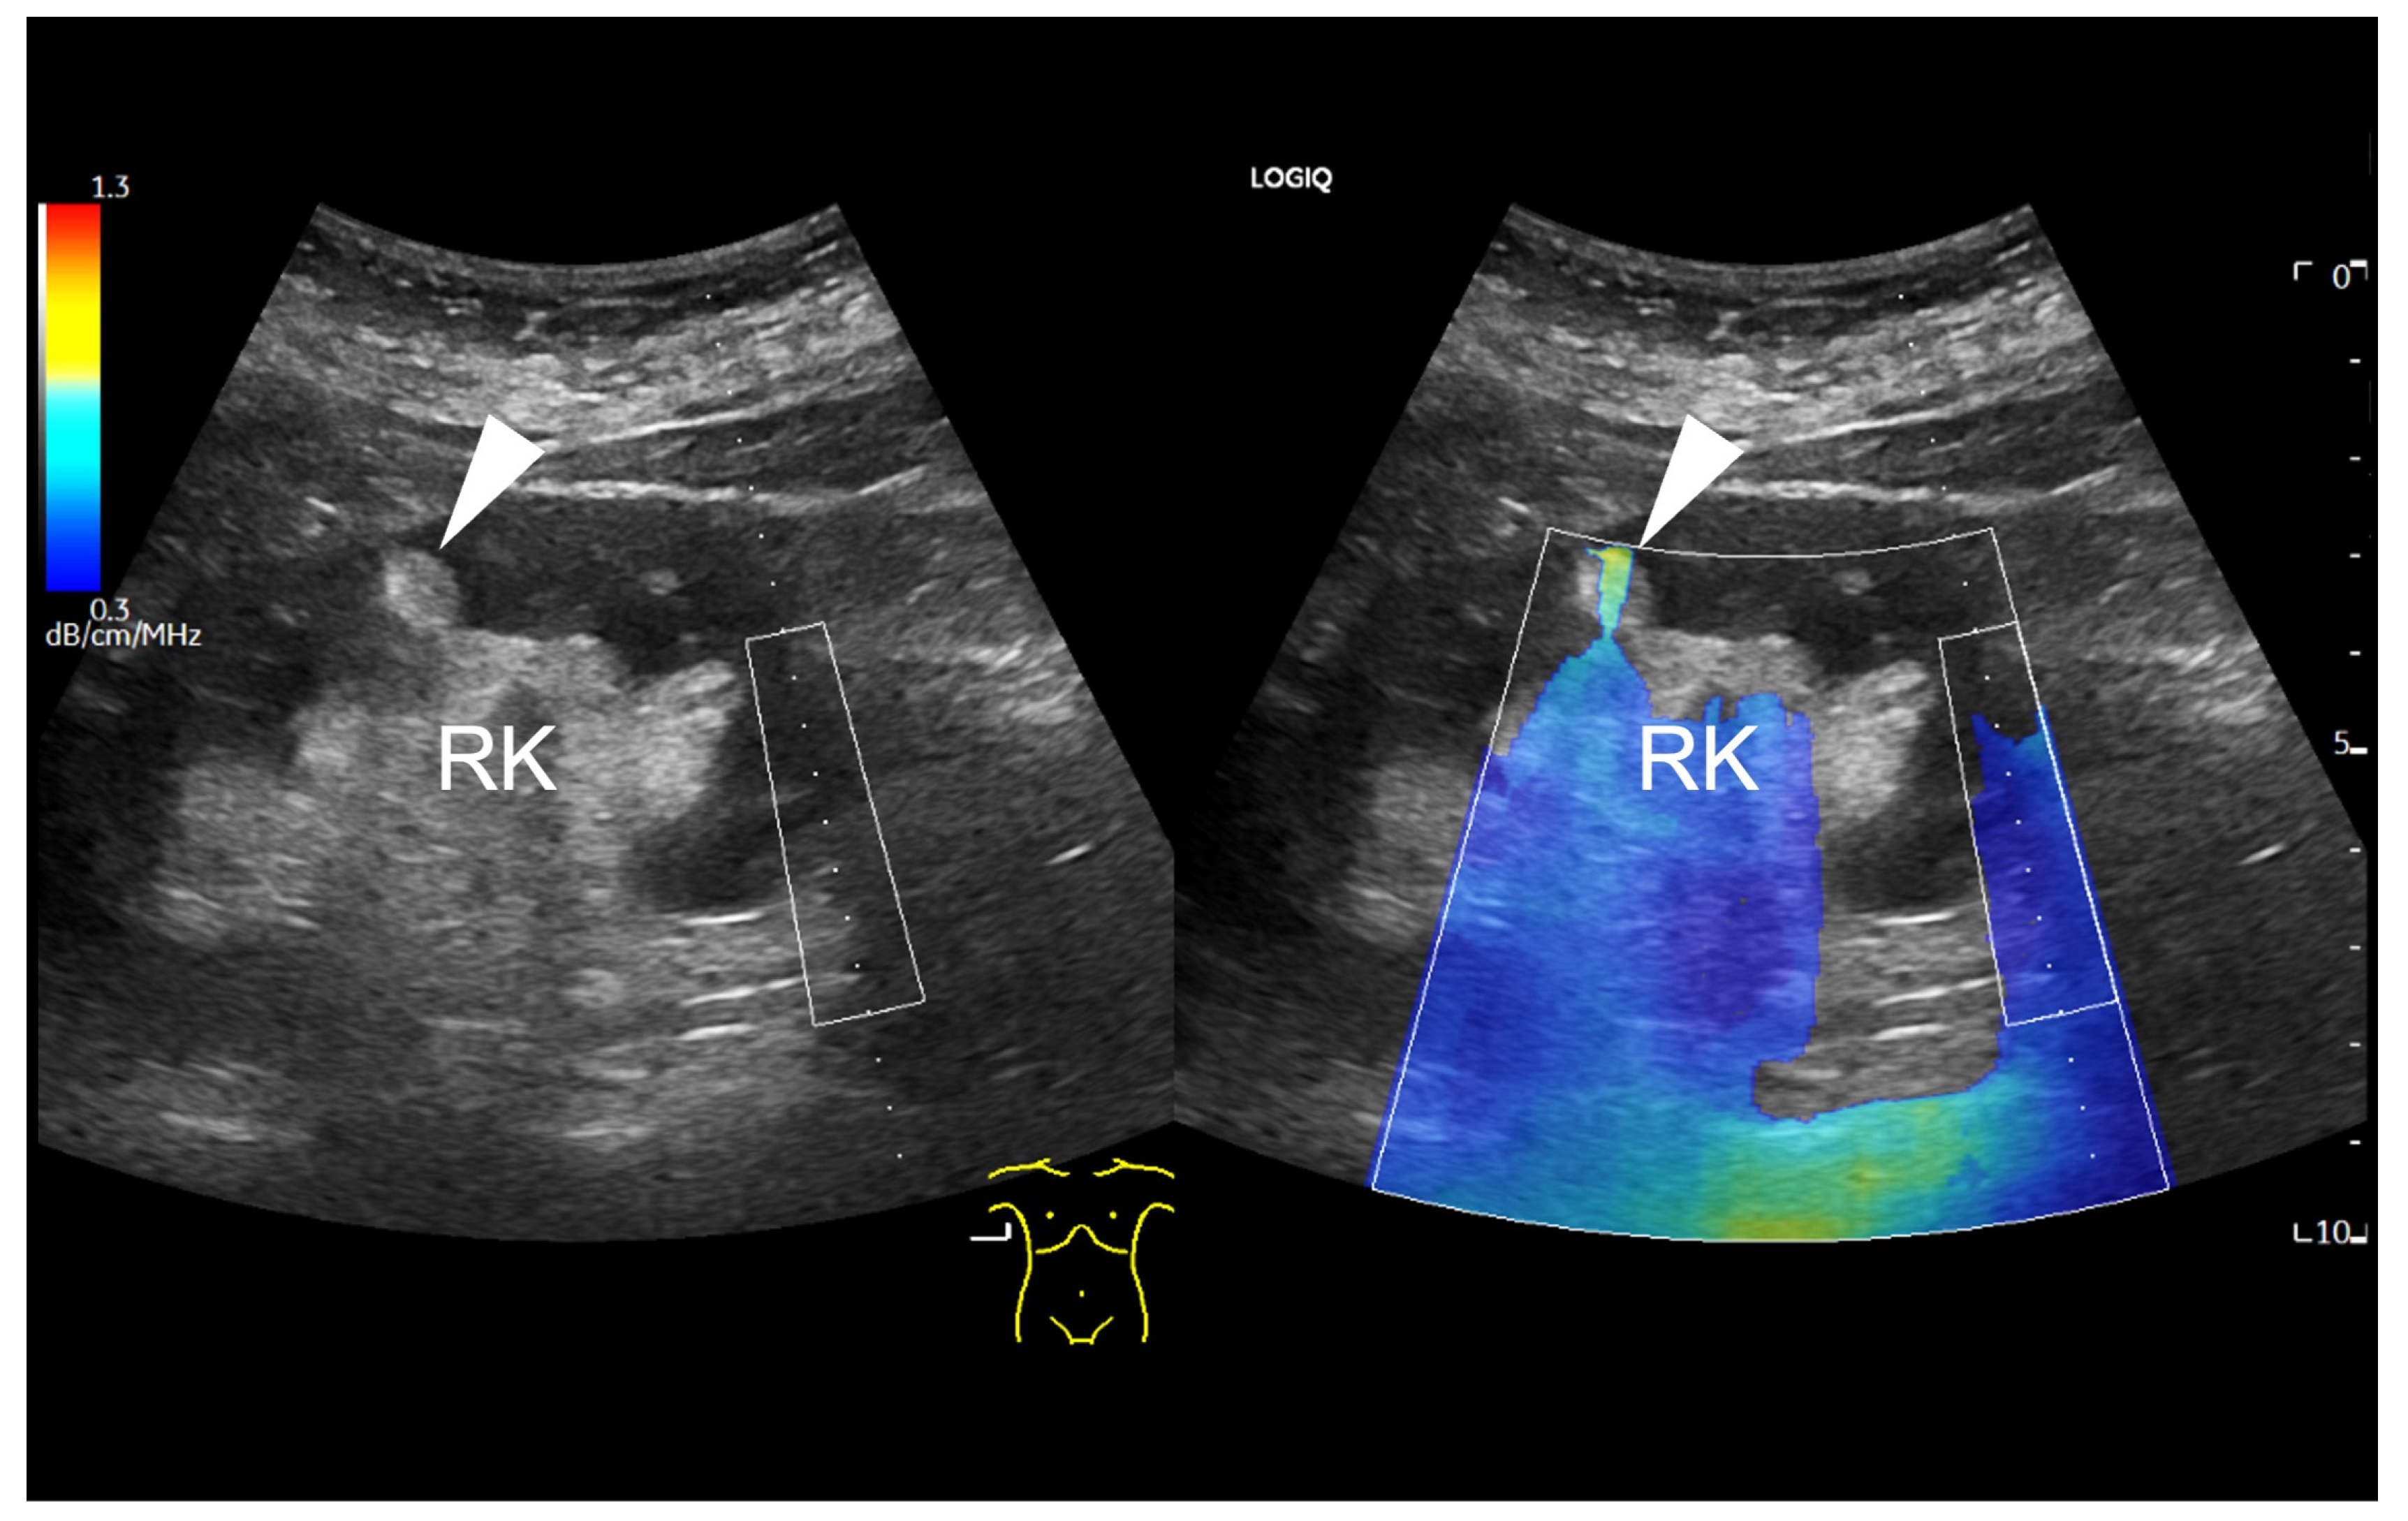

First, UGAP was used qualitatively. Using the quality map option, the color-coded map was placed right above the lesion. A positive finding was defined by a significant difference in the colour map above the lesion (red-yellow) compared to the surrounding tissue. This is shown for example in Figure 1.

Figure 1.

B-mode ultrasound image showing a focal hyperechoic lesion (arrowhead) in the cortex of the right kidney (RK). In the attenuation map on the right side, the lesion appears in red and yellow, representing a higher attenuation than the surrounding tissue. The level of attenuation is shown color-coded on the scale on the top left corner of the image. Next to the right kidney, the liver (L) is displayed. A region of interest (ROI) box is displayed above the hyperechogenic lesion.